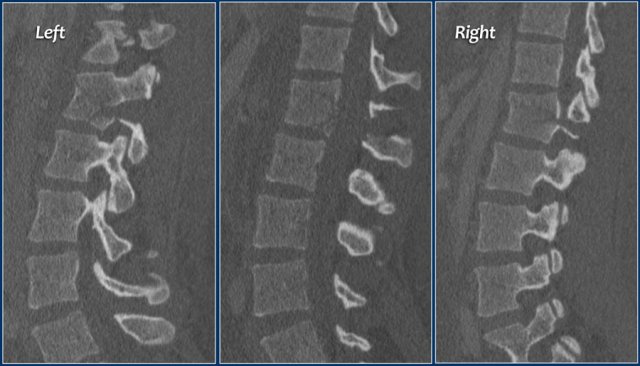

The findings are:

• Morphology: Distraction- 4 points

• PLC: always disrupted in distraction on posterior side - 3 points

• TLICS: 7 points

1. Morphology: Distraction - 4 points

2. PLC: always torn in posterior distraction - 3 points

3. TLICS based on imaging: 7 points

The key point in this case is that you should not describe this morphology as burst - 2 points.

The horizontal fractures on the posterior side and the increased interspinous distance indicate distraction, which means a higher score for morphology.

Always go for the highest possible score in TLICS.